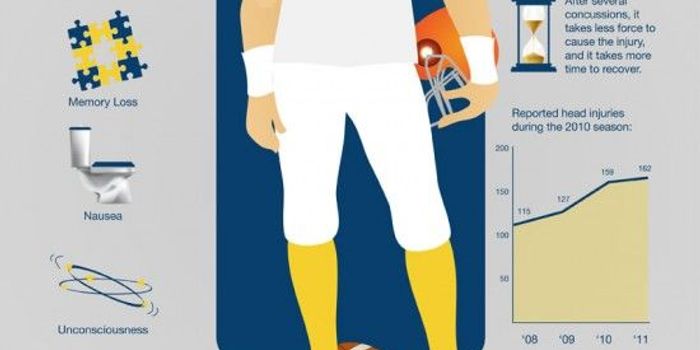

JUN 01, 2016NeuroscienceThe saga of the NFL and its responsibility for traumatic brain injuries to players continued this week with a report fro ...

MAR 23, 2016NeuroscienceWhile the subject of brain injuries, concussion and Chronic Traumatic Encephalopathy (CTE) have swirled around the NFL f ...

FEB 16, 2016NeuroscienceAlmost every week there is another item in the news about head injuries in major league sports, most prominently t ...

OCT 07, 2015NeuroscienceThe NFL is known for a lot of things. Big players tackling each other, cheerleaders, the Super Bowl, and sadly, for inju ...